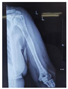

患者女性,50岁,于2020年4月无明显诱因出现左上臂肿痛,活动受限等症状,自行休息后未见明显缓解,遂就诊于当地医院,行X光片提示:左肱骨上段骨质破坏(图1)。后于2020年4月30日行PET/CT全身显像(图2)提示:甲状腺左侧叶混杂密度结节,代谢稍活跃;双肺多发结节,代谢活性未见明显增高;下颌骨右侧支、左侧肱骨上段、左侧耻骨及第4腰椎棘突骨质破坏,代谢活跃。为进一步明确诊断,患者于2020年5月14日在外院行"左肱骨中上段肿瘤广泛切除,人工肱骨头置换术",术后病理提示:符合甲状腺滤泡性癌转移。遂于2020年6月1日再次于该院行"双侧甲状腺全部切除术+颈部淋巴结清扫术(Ⅲ、Ⅳ及Ⅶ区)+喉返神经探查术",术后病理(图3)提示:1、(左侧甲状腺)广泛浸润性甲状腺滤泡癌,肿瘤大小5.0 cm×4.0 cm×2.0 cm,血管浸润>4个血管,未见明确神经侵犯;2、(右侧甲状腺)甲状腺滤泡性肿瘤,考虑为滤泡癌累及。为进一步治疗,患者于2020年7月28日、2021年1月13日入住我院行131I治疗。